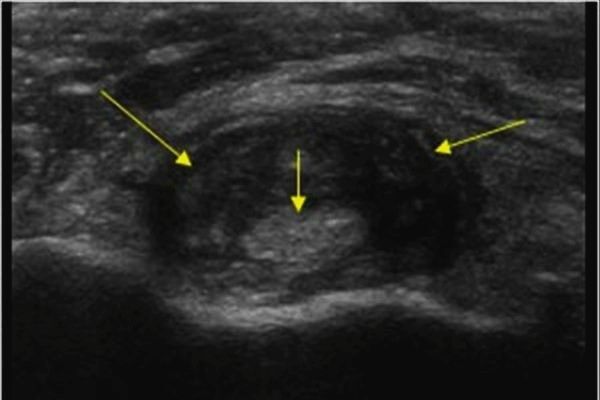

На УЗИ - “двойной контур” признаки отложения кристаллов, синовит во время приступа - могут обнаружены случайно до развития приступа.

Двойной контур на УЗИ, свидетельствует об отложении кристаллов мочевой кислоты.